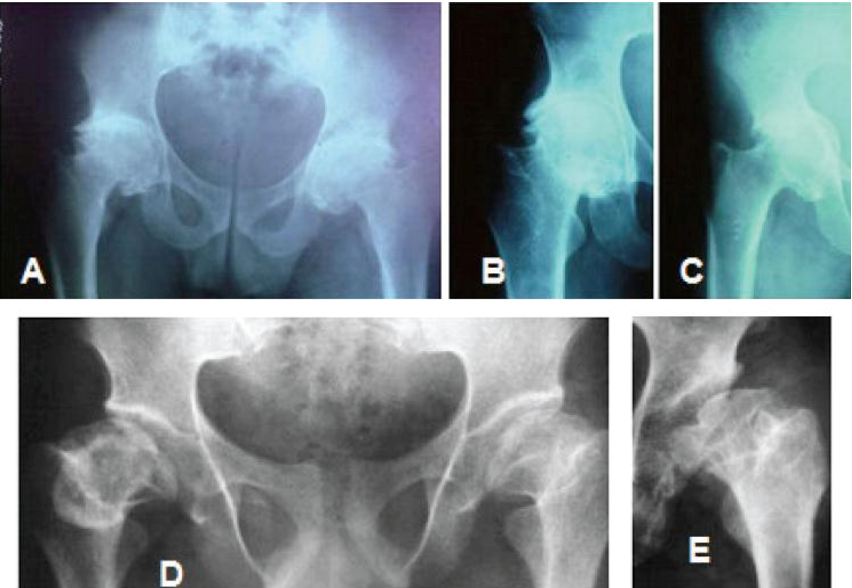

Handigodu Disease (HD) is a rare, chronic skeletal disorder primarily reported in certain regions of Karnataka. Named after the Handigodu village where it was first identified, this disease has significant implications for public health and medical research.

It primarily affects bones and joints leading to deformities, disability and chronic pain. Scientific studies aim to uncover the genetic, environmental and biochemical factors contributing to this disorder.

Severe pain in joints and bones particularly in the hip and knee.

Early-onset osteoarthritis leading to deformities.